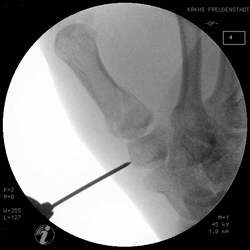

Basisfraktur des 1. Mittelhandknochen

Wenn die Frakturstellung nach Reposition und Ligamentotaxis

gut ist, kann die Fraktur mit einem gelenküberbrückenden Microfixateur

stabilisiert werde.

Die Frakturkontrolle muß in allen Ebenen kontrolliert

werden.